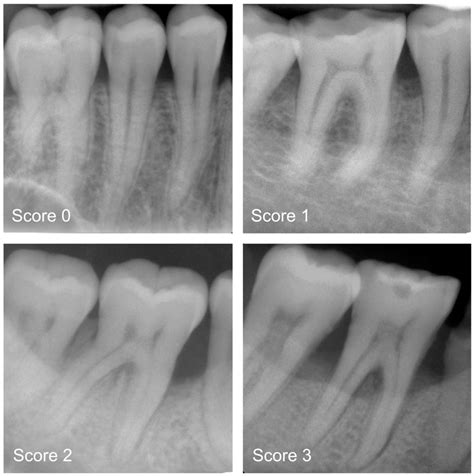

Dental professionals use various imaging techniques to determine the extent of Dental Bone Loss. The progression is typically categorized based on how much height or width the bone has lost. Below is a breakdown of how this impact is generally viewed:

Stage Description Clinical Impact

Early Minimal reduction in bone height Usually asymptomatic; visible on X-rays.

Moderate Noticeable loss of bone density Teeth may feel slightly loose or shift.

Advanced Significant loss of structure Visible facial sagging and high tooth mobility.

⚠️ Note: Regular dental check-ups with digital X-rays are the only way to detect the early stages of bone resorption before physical symptoms appear.